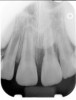

Fig 3. Postoperative radiograph.

Figure 3

Clinical procedure: If apical bone loss is present (Figure 1) a collagen/gelatin sponge (eg, Gelfoam®, Pfizer Inc., www.pfizer.com) can be placed apically so that the MTA can be delivered to the desired working length. (Any other surgical resorbable sponge would also work, such as OraPlug® [Salvin Dental Specialties, www.salvin.com], Surgifoam® [Midwest Dental, www.mwdental.com], or Surgispon® [Aegis Lifesciences, www.surgispon.com]). This is done by taking a small piece (2 mm x 2 mm) of the resorbable sponge and pushing it down to and through the root apex with an endodontic file. Once this is done, MTA is packed down the canal with a custom-fitted cone. The clinician can use a rubber stopper on the gutta-percha cone to know the exact length of MTA placed in the apical third (Figure 2). Once the apical third is sealed with 3 mm to 5 mm of MTA, the remaining coronal canal space can be back-filled using a warm gutta-percha technique (Figure 3).